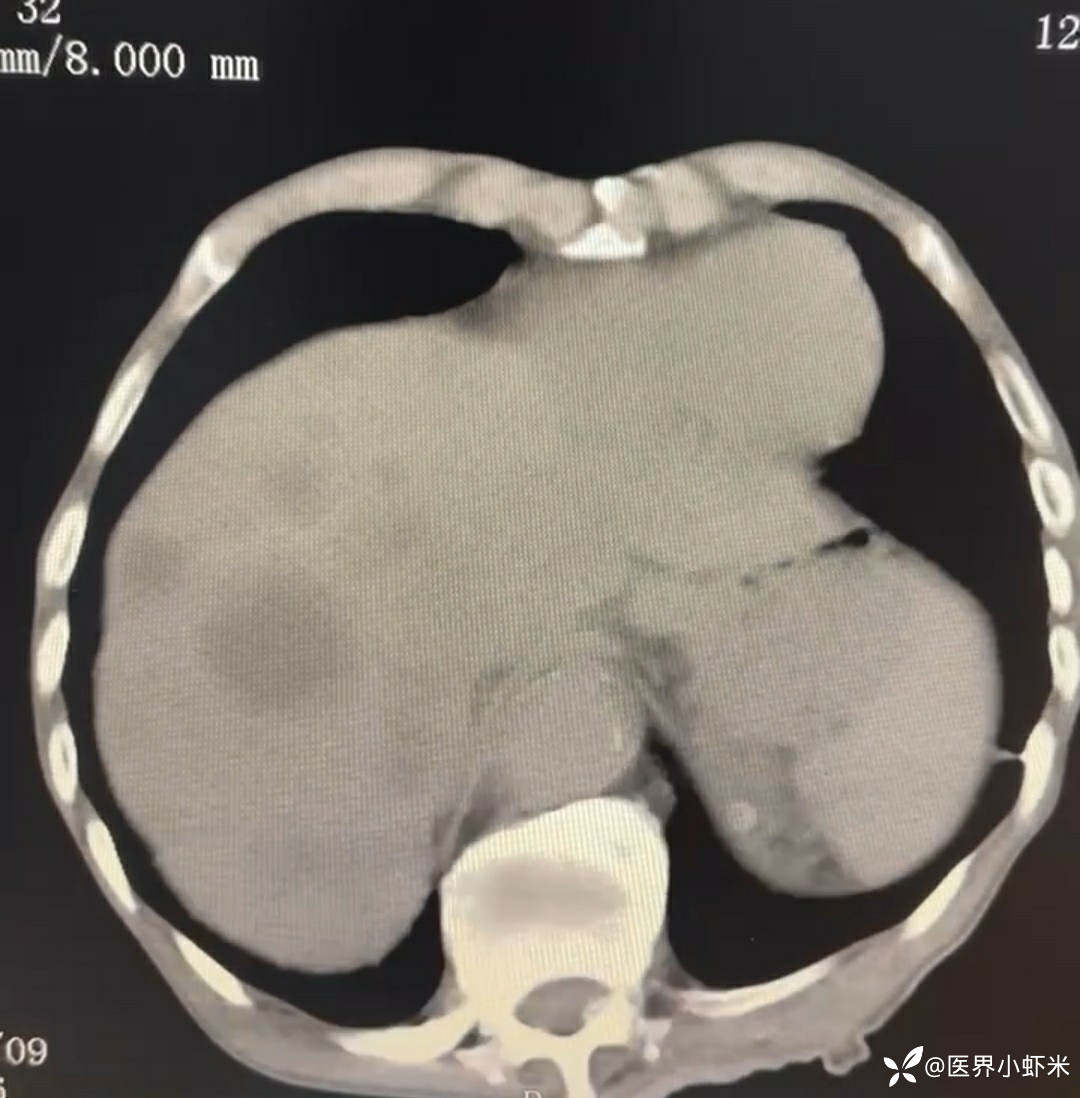

目前考虑:1.中央型肺癌伴2.肝继发恶性肿瘤?2.左丘脑继发恶性肿瘤?3.左丘脑出血?4.肾功能不全5.肝功能异常6右肾萎缩7.肺部感染8.慢性阻塞性肺病7.高血压3级(极高危)。